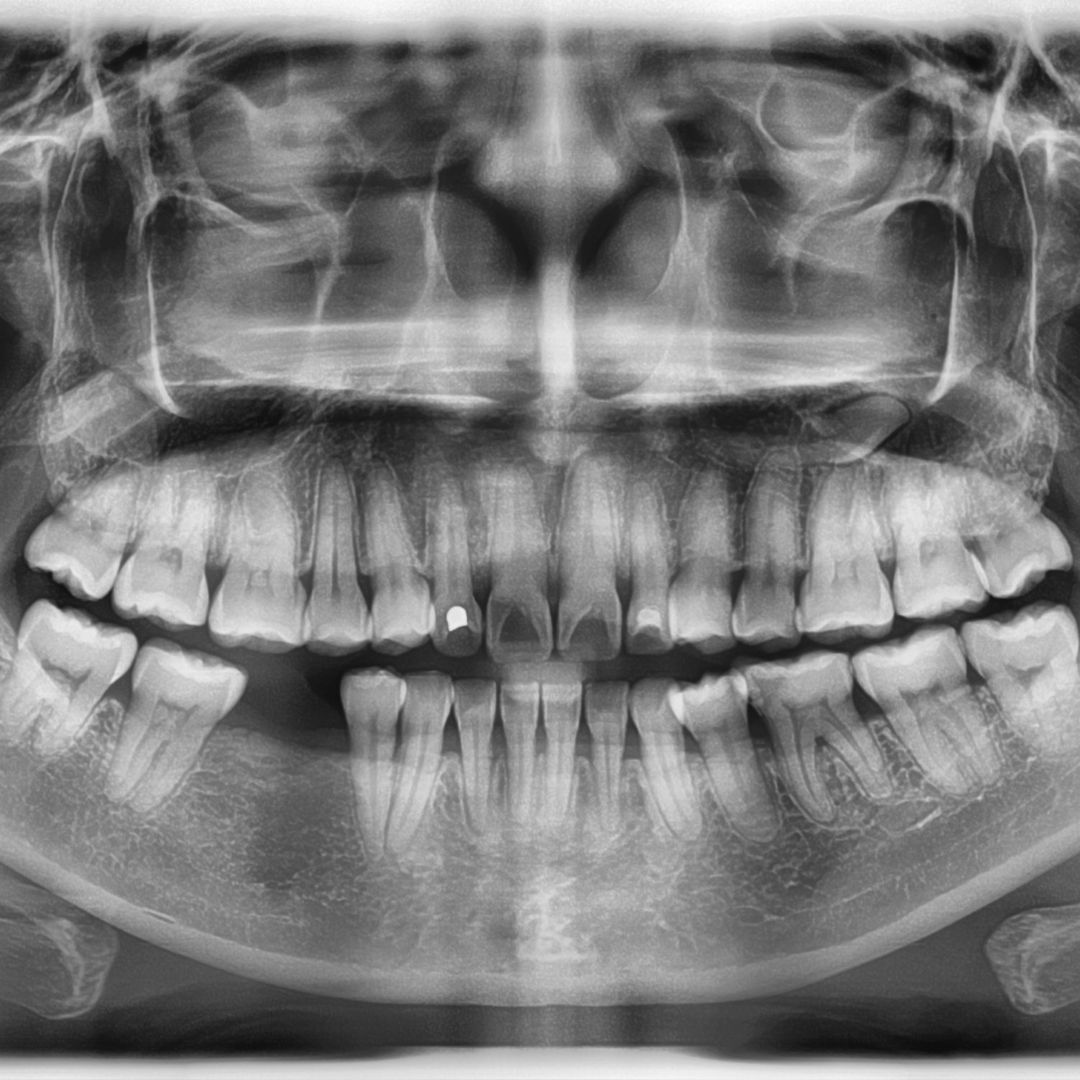

The progression from gingivitis to periodontitis involves the deepening of periodontal pockets, loss of epithelial attachment, and destruction of the periodontal ligament. Radiographically, this manifests as horizontal or vertical bone loss patterns, with the severity correlating with the degree of inflammation and bacterial load. Risk factors such as poor oral hygiene, smoking, and genetic predisposition (e.g., IL-1 gene polymorphisms) exacerbate the condition, accelerating bone resorption.

Endodontic infections, such as periapical abscesses, can lead to localized bone loss. The spread of infection from the pulp to the periapical region triggers an inflammatory response, resulting in osteoclastic resorption of the surrounding bone. Radiographically, this appears as a periapical radiolucency. Similarly, odontogenic cysts and tumors, such as ameloblastomas or odontogenic keratocysts, cause expansive bone destruction through local invasion and pressure resorption.